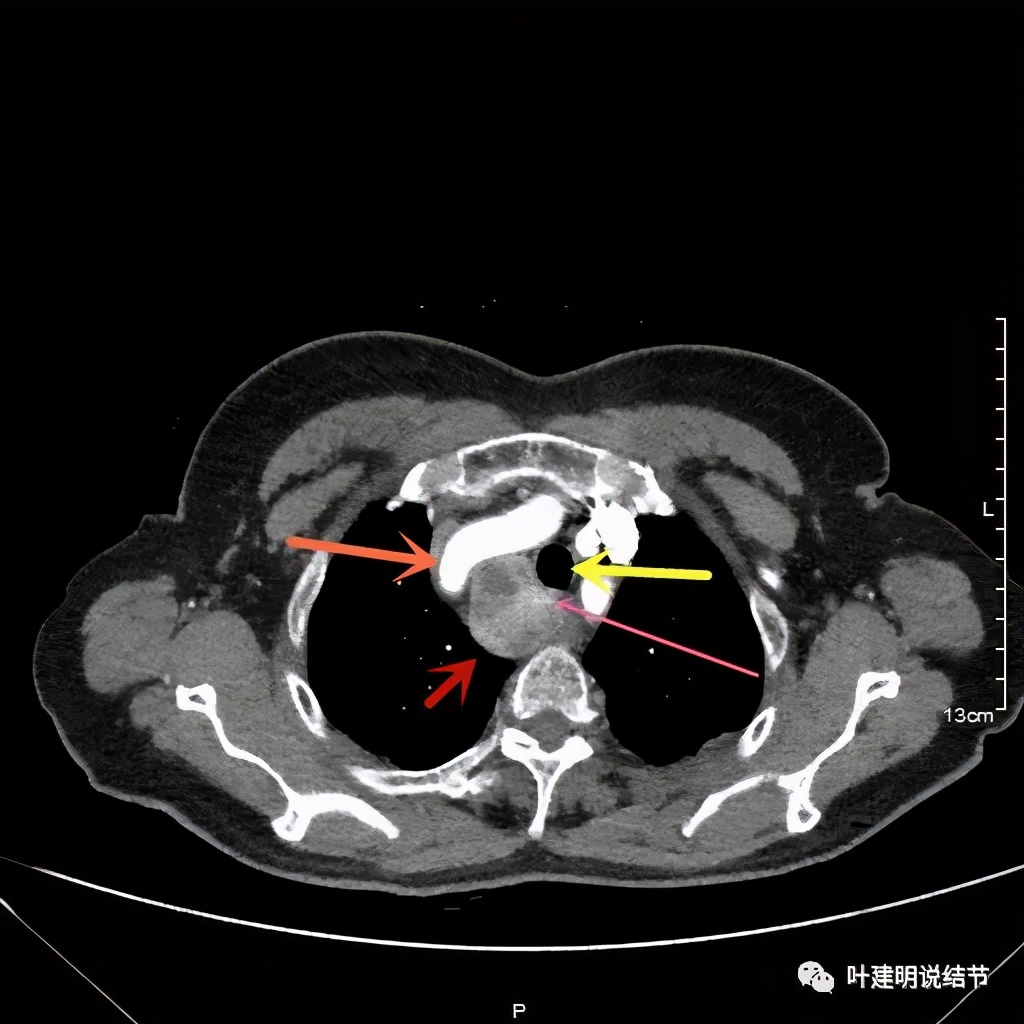

上图红色示肿瘤,黄色示气管,粉色示肿瘤与气管关系密切,桔色示左无名静脉,蓝色示上腔静脉,而且肿瘤密度不均杂乱

上图红色示肿瘤,黄色示气管,桔色示左无名静脉,蓝色示上腔静脉,而且肿瘤密度不均杂乱

上图红色示肿瘤,黄色示气管,粉色示肿瘤与气管关系密切,桔色示左无名静脉,肿瘤密度不均

上图红色示肿瘤,黄色示气管,蓝色示上腔静脉